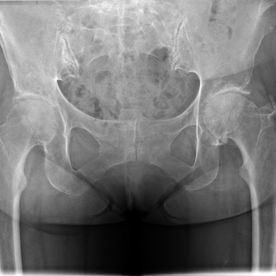

Coxarthrose (Hüftverschleiß)